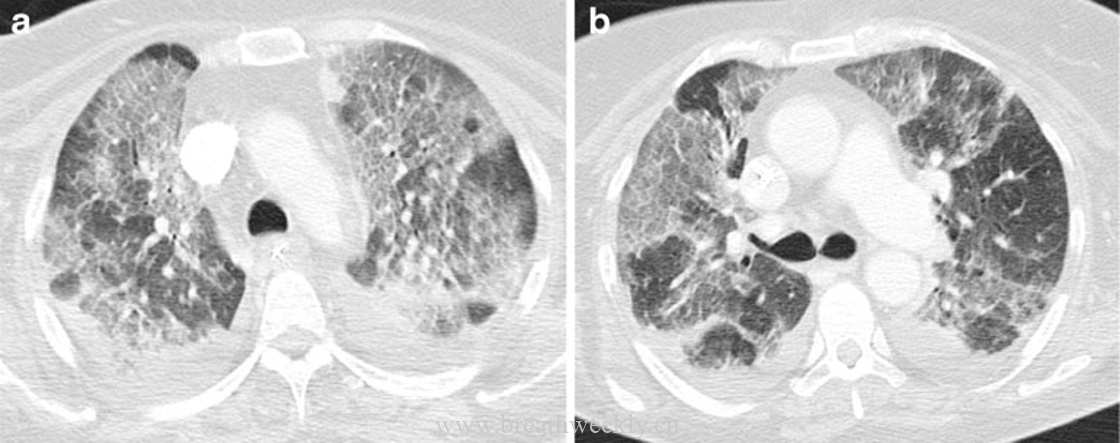

病例9:ARDS

临床资料:67岁女性,全膝关节置换术后发生感染性休克伴ARDS。

影像表现:CT显示双肺磨玻璃影叠加网状影。

病例10:肺水肿

临床资料:83岁男性,急性淋巴细胞性白血病,心功能不全。

影像表现:CT显示斑片状磨玻璃影叠加线状影,小叶内血管扩张呈蜘蛛样。

ARDS是肺水肿的一种形式。CT特征为双肺实变和磨玻璃影,也可见网状和线状影。组织学特征包括肺泡和血管周围水肿,肺泡内富含蛋白的液体填充。进展至结构扭曲和蜂窝肺伴小叶间隔增厚导致线状影。